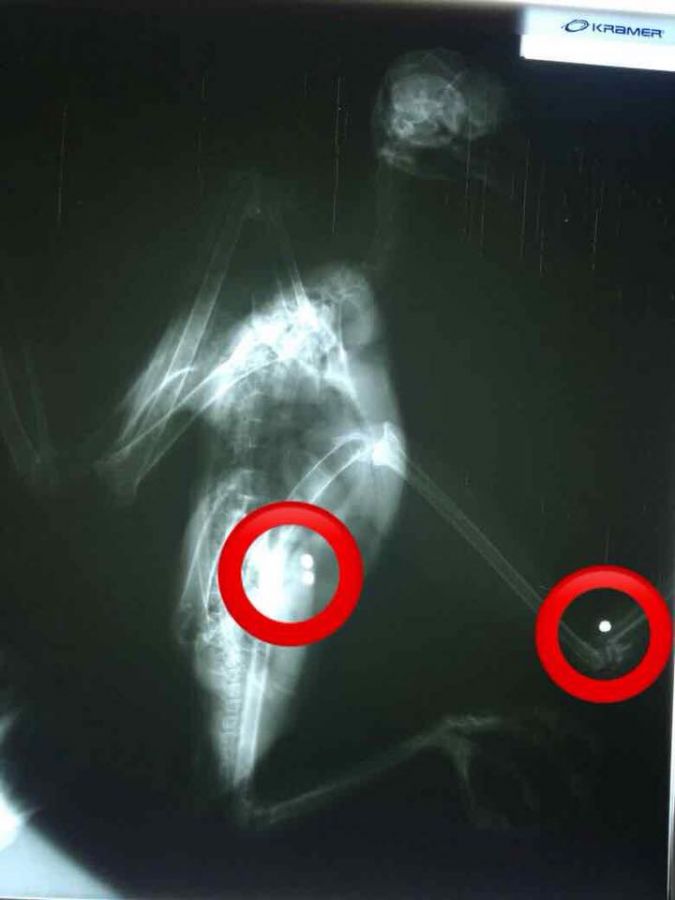

La persona que la entregó, presume haberla encontrado en la puerta de su casa, en el Corregimiento San José de la Paz. El Águila Crestada (Spizaetus isidori) presenta dos perdigones alojados en su muslo y un tercero que ocasionó fractura de su pata izquierda. En este momento, el equipo de la Red de Fauna y Flora Silvestre de @corpocesar se encuentra a la espera de veterinarios expertos en este tipo de rapaces para realizar la intervención y lograr salvar este individuo que luego de su recuperación sería devuelto a su hábitat. #ElDato | Está es la ave rapaz en mayor peligro de extinción en el país seguida por la Águila solitaria.